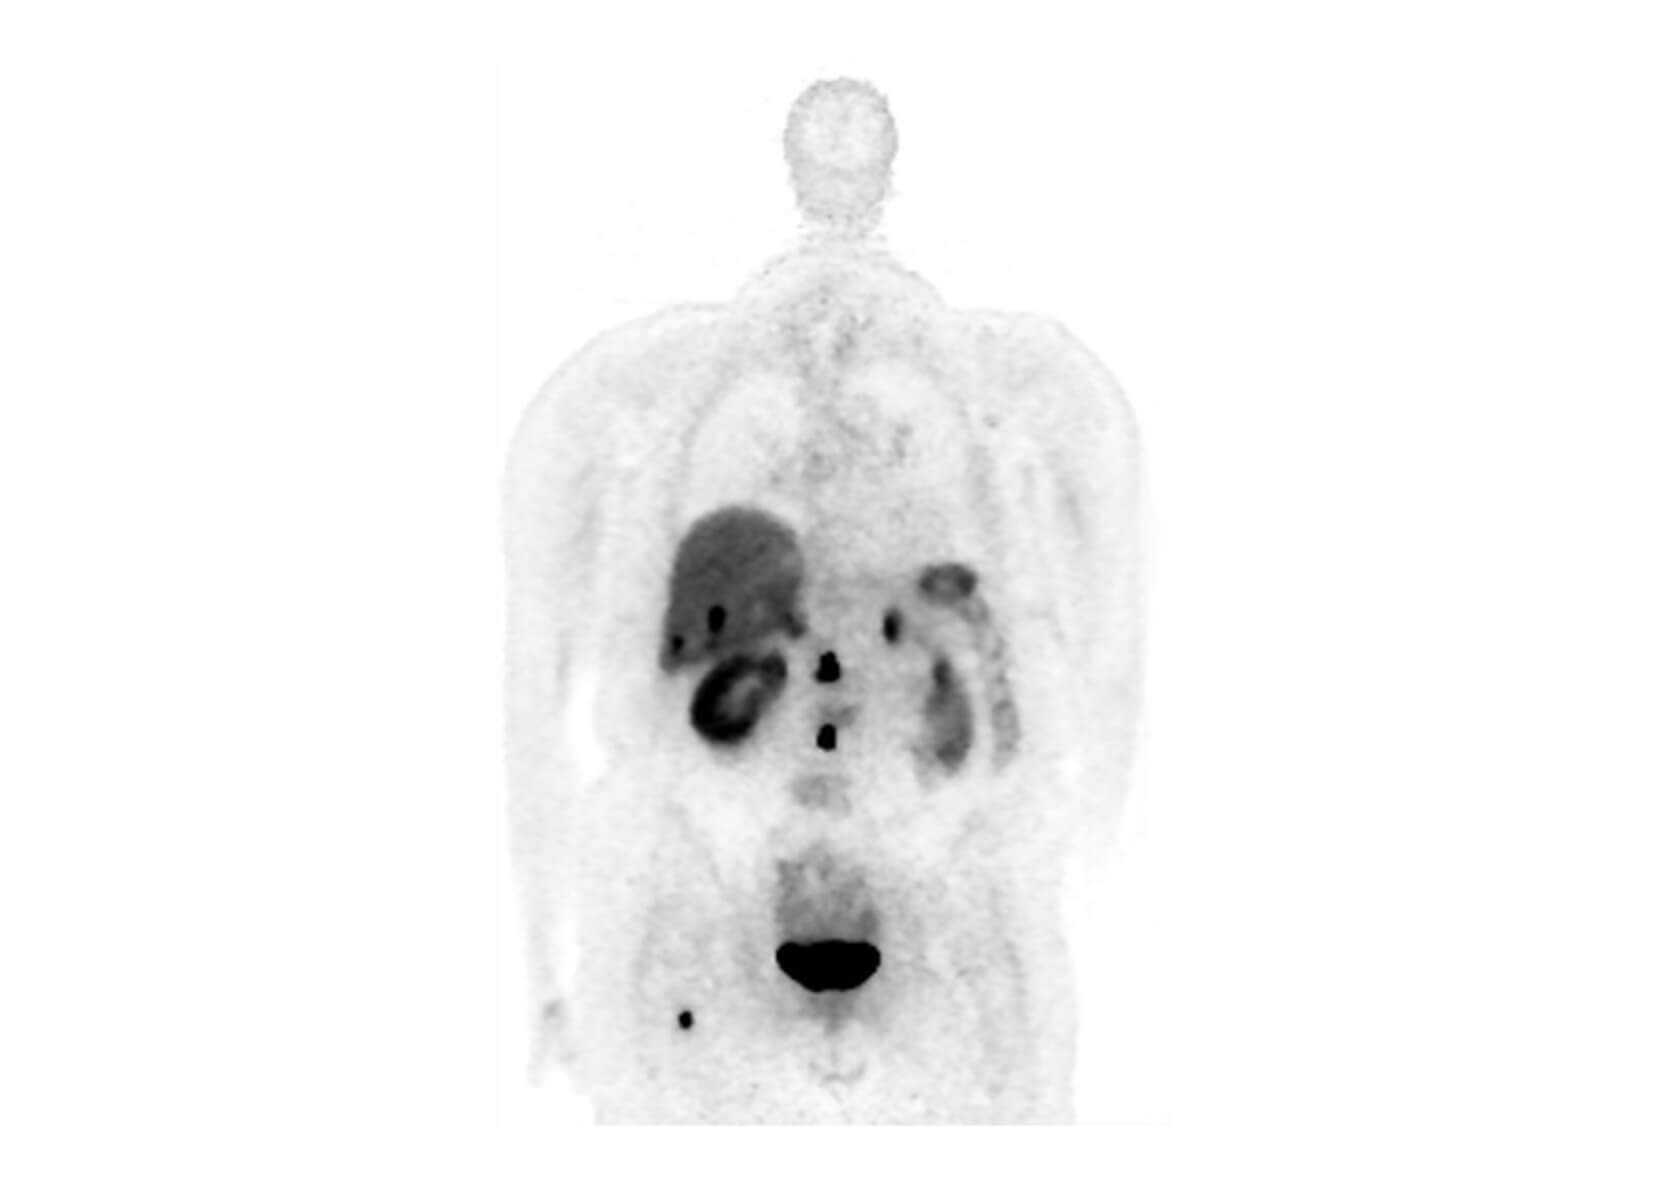

Conventional

ACQ TIME:

20 min

SubtleHD™(PET)

5 min

18F-Florbetapir (AMYLOID)

Philips Vereos PET/CT